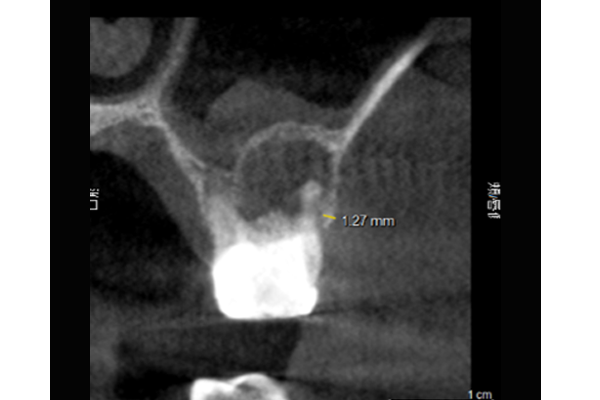

レントゲン写真

⚫︎根の先端に大きな病変があります。

⚫︎治療を行って治癒する見込みが低い状態です。

⚫︎前後の歯は削りたくないので、今後インプラント治療を行なっていきます。